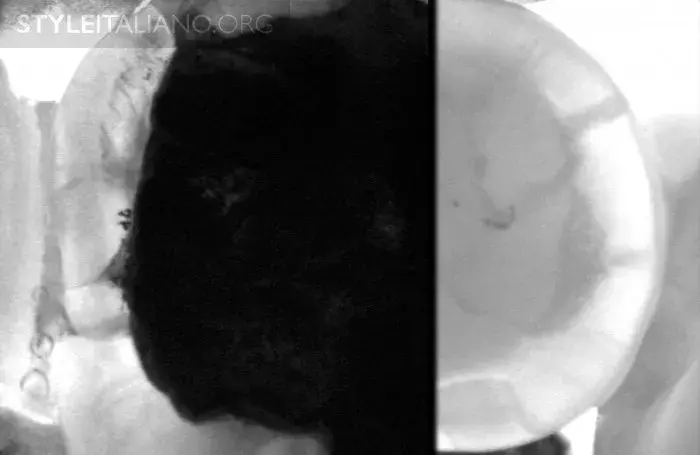

Рис. 15 — Предоперационный вид/ Лазерное просвечивание/ Рентген.

Рис. 16 – Просвечивание зубов показывает полости в истинном размере, а на рентгене они уменьшены.

Рис. 17 – Рентген слева, просвечивание справа.